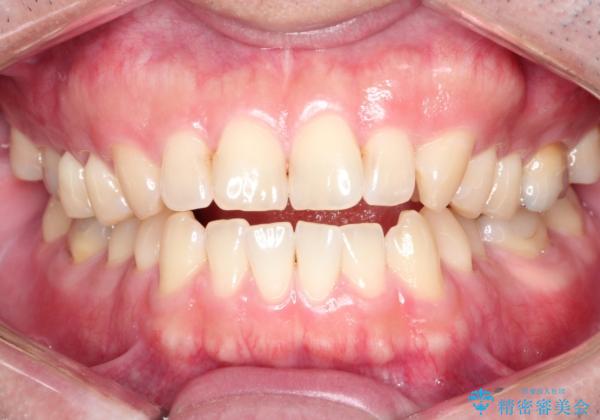

マウスピース矯正で自然な笑顔を実現! 前歯の咬み合わせを治しました。

- 前歯の咬み合わせが気になるとのことで来院されました。

前歯が噛んでいない状態(開咬)のため、インビザライン矯正で改善することとしました。